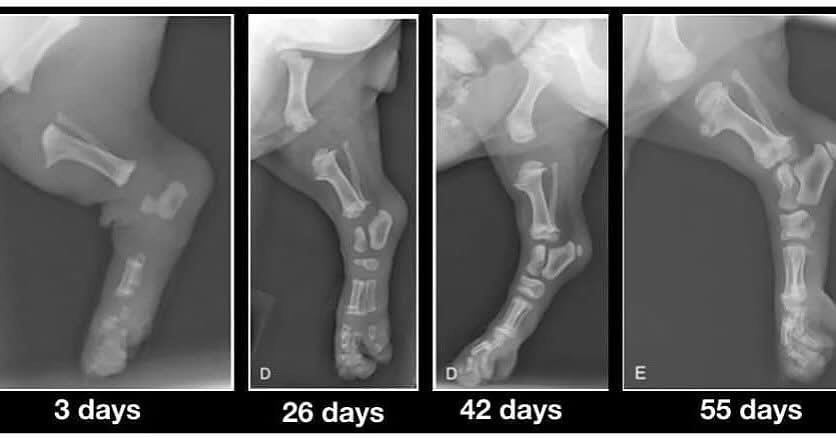

Ich greife dieses Thema auf, weil ich ein sehr

ausdruckstarkes Röntgenbild im Internet gefunden habe, wo die Knochen von

Welpen verschiedenen Alters dargestellt werden. Hier kann man sehr gut

sehen, wie die Knochenbildung voranschreitet. Es sieht so aus, als ob die

Knochenteile ohne Verbindung miteinander sind, doch die Gelenkknorpel

sieht man auf den Röntgenbildern nicht. Diese sogenannten Wachstumsfugen (

Epiphysenfugen ) sind noch nicht geschlossen und die Gelenkköpfe sind sehr

weich und empfindlich! Das Knochenwachstum wird durch sogenannte

Osteoblasten, die für das Einlagern von Calziumphosphat verantwortlich

sind. Soweit zum Längenwachstum; die Knochendicke erfolgt durch

Anlagerung.